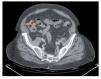

Se trata de un hombre de 83 años de edad, fumador, sin antecedentes personales quirúrgicos ni otros relevantes. Acudió por presentar un cuadro de 18 horas de evolución caracterizado por dolor abdominal tipo cólico, en epigastrio y mesogastrio, de moderada intensidad, sin irradiación, acompañado de náusea y vómito en posos de café en varias ocasiones, malestar general, astenia, adinamia. Al interrogatorio intencional, informó haber ingerido ciruelas en abundante cantidad cuatro días antes de su ingreso. A la exploración física se encontró afebril, con frecuencia cardiaca y tensión arterial normal, saturación de oxígeno de 88% al aire ambiente y 94% con suplemento de oxígeno al 40%, rubicundo, tórax en tonel, con campos pulmonares hipoventilados. Abdomen muy distendido, peristalsis disminuida de tonalidad metálica, poco depresible, timpánico y con datos de irritación peritoneal (signo de "rebote" positivo). Los exámenes de laboratorio mostraron hemoglobina 19.1mg/ dL, hematocrito 56.2%, leucocitos 14 500 células/ mm3, proteína C reactiva positiva. Las radiografías simples de abdomen mostraron evidentes niveles hidroaéreos así como distensión de asas de intestino delgado (Figura 1). La tomografía computarizada de abdomen con doble contraste demostró punto de transición a 60 cm de válvula ileocecal así como niveles hidroaéreos (Figura 2). Se colocó sonda nasogástrica para descompresión y se realizó laparoscopía diagnóstica mano asistida durante la cual se ubicó el sitio de transición 60 cm a 70 cm de válvula ileocecal y se palpó una masa móvil intraluminal. Se realizó enterotomía y se extrajo una masa de color amarillento, de aproximadamente tres por cuatro centímetros que se envió a patología, reportando fitobezoar (Figuras3 y 4). La evolución fue favorable y el paciente egresó al séptimo día del postoperatorio.

¿ Figura 2. Imagen de tomografía en la que se hace evidente el punto de transición (flecha).